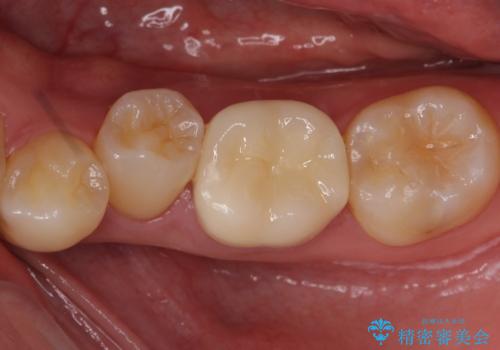

奥歯の詰め物の変色 セラミッククラウンでのやり替え

樹脂の材料はどうしても変色などの劣化スピードが速いです。

樹脂の変色が気になる場合は、劣化しにくいセラミックに材料ごと変えることをお勧めします。